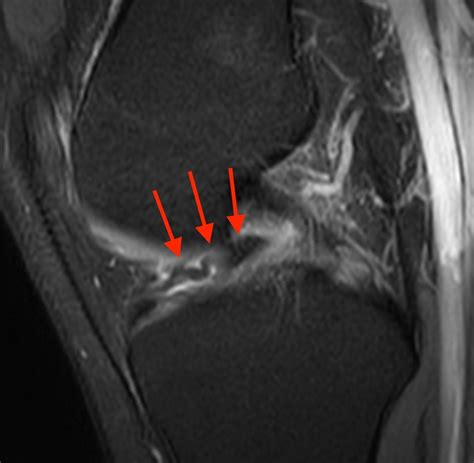

A Bucket Handle Injury is a specific type of meniscal tear that occurs in the knee. The meniscus is a C-shaped piece of cartilage that acts as a shock absorber between the thighbone (femur) and the shinbone (tibia). When a tear occurs in a way that the inner portion of the meniscus flips up into the joint, it is called a bucket handle tear because it resembles the handle of a bucket.

• MRI (Magnetic Resonance Imaging): To provide detailed images of the soft tissues, including the meniscus, to confirm the diagnosis.

• Arthroscopy: A minimally invasive procedure where a small camera and surgical tools are inserted into the knee joint to repair or remove the torn meniscus.